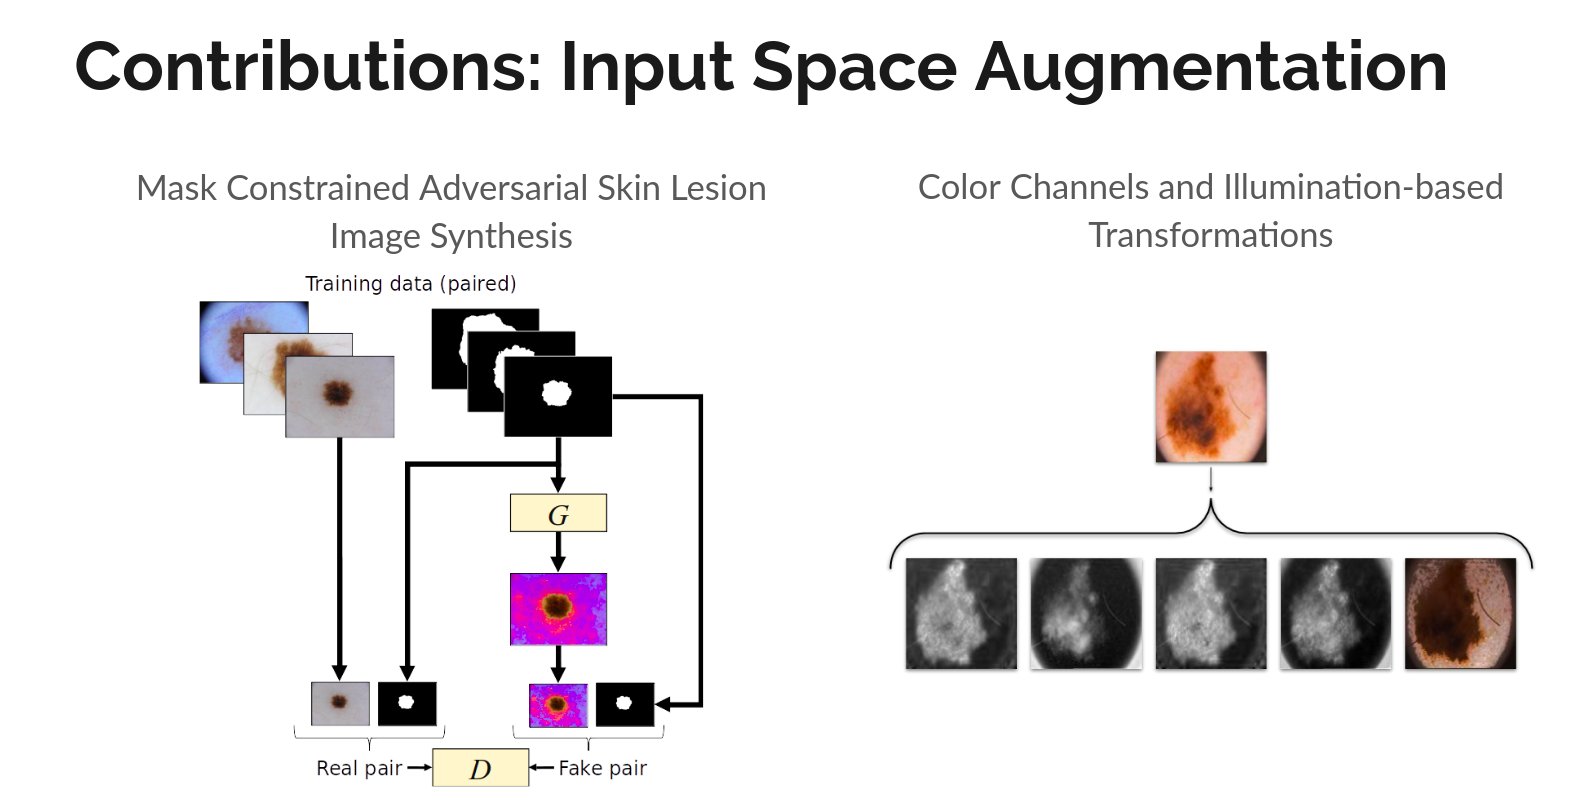

Input Space Augmentation for Skin Lesion Segmentation in Dermoscopic Images

Master's Thesis

[Abstract] [BibTeX]

Cancer is the second leading cause of death globally, and of all the cancers, skin cancer is the most prevalent. Early diagnosis of skin cancer is a crucial step for maximizing patient survival rates and treatment outcomes. Skin conditions are often diagnosed by dermatologists based on the visual properties of the affected regions, motivating the utility of automated algorithms to assist dermatologists and offer viable, low-cost, and quick results to assist dermatological diagnoses. Over the last decade, machine learning, and more recently, deep learning-based diagnoses of skin lesions have started approaching human performance levels. This thesis studies approaches to improve the segmentation of skin lesions in dermoscopic images, which is often the first and the most important task in the diagnosis of dermatological conditions. In particular, we present two methods to improve deep learning-based segmentation of skin lesions by augmenting the input space of convolutional neural network models. In the first contribution, we address the problem of the paucity of annotated data by learning to synthesize artificial skin lesion images conditioned on input segmentation masks. We then use these synthetic image mask pairs to augment our original segmentation training datasets. In our second contribution, we leverage certain color channels and skin imaging- and illumination-based knowledge in a deep learning framework to augment the input space of the segmentation models. We evaluate the two contributions on five dermoscopic image datasets: the ISIC Skin Lesion Segmentation Challenge 2016, 2017, and 2018 datasets, the DermoFit Image Library, and the PH2 Database, and observe performance improvements across all datasets.

Illumination-based Transformations Improve Skin Lesion Segmentation in Dermoscopic Images

Kumar Abhishek, Ghassan Hamarneh, Mark S. Drew

ISIC Skin Image Analysis Workshop, IEEE International Conference on Computer Vision and Pattern Recognition (CVPR), 2020 We incorporate information from specific color bands, illumination invariant grayscale images, and shading-attenuated images obtained from RGB dermoscopic images of skin lesions to improve the lesion segmentation. [Abstract] [BibTeX] [Presentation Slides]

The semantic segmentation of skin lesions is an important and common initial task in the computer aided diagnosis of dermoscopic images. Although deep learning-based approaches have considerably improved the segmentation accuracy, there is still room for improvement by addressing the major challenges, such as variations in lesion shape, size, color and varying levels of contrast. In this work, we propose the first deep semantic segmentation framework for dermoscopic images which incorporates, along with the original RGB images, information extracted using the physics of skin illumination and imaging. In particular, we incorporate information from specific color bands, illumination invariant grayscale images, and shading-attenuated images. We evaluate our method on three datasets: the ISBI ISIC 2017 Skin Lesion Segmentation Challenge dataset, the DermoFit Image Library, and the PH2 dataset and observe improvements of 12.02%, 4.30%, and 8.86% respectively in the mean Jaccard index over a baseline model trained only with RGB images.

Mask2Lesion: Mask-Constrained Adversarial Skin Lesion Image Synthesis

Kumar Abhishek, Ghassan Hamarneh

Workshop on Simulation and Synthesis in Medical Imaging (SASHIMI), International Conference on Medical Image Computing and Computer Assisted Intervention (MICCAI), 2019 We propose a GAN-based synthesis approach for generating realistic skin lesion images from lesion masks, making it an appropriate augmentation strategy for skin lesion segmentation datasets. [Abstract] [BibTeX] [Poster]

Skin lesion segmentation is a vital task in skin cancer diagnosis and further treatment. Although deep learning based approaches have significantly improved the segmentation accuracy, these algorithms are still reliant on having a large enough dataset in order to achieve adequate results. Inspired by the immense success of generative adversarial networks (GANs), we propose a GAN-based augmentation of the original dataset in order to improve the segmentation performance. In particular, we use the segmentation masks available in the training dataset to train the Mask2Lesion model, and use the model to generate new lesion images given any arbitrary mask, which are then used to augment the original training dataset. We test Mask2Lesion augmentation on the ISBI ISIC 2017 Skin Lesion Segmentation Challenge dataset and achieve an improvement of 5.17% in the mean Dice score as compared to a model trained with only classical data augmentation techniques.